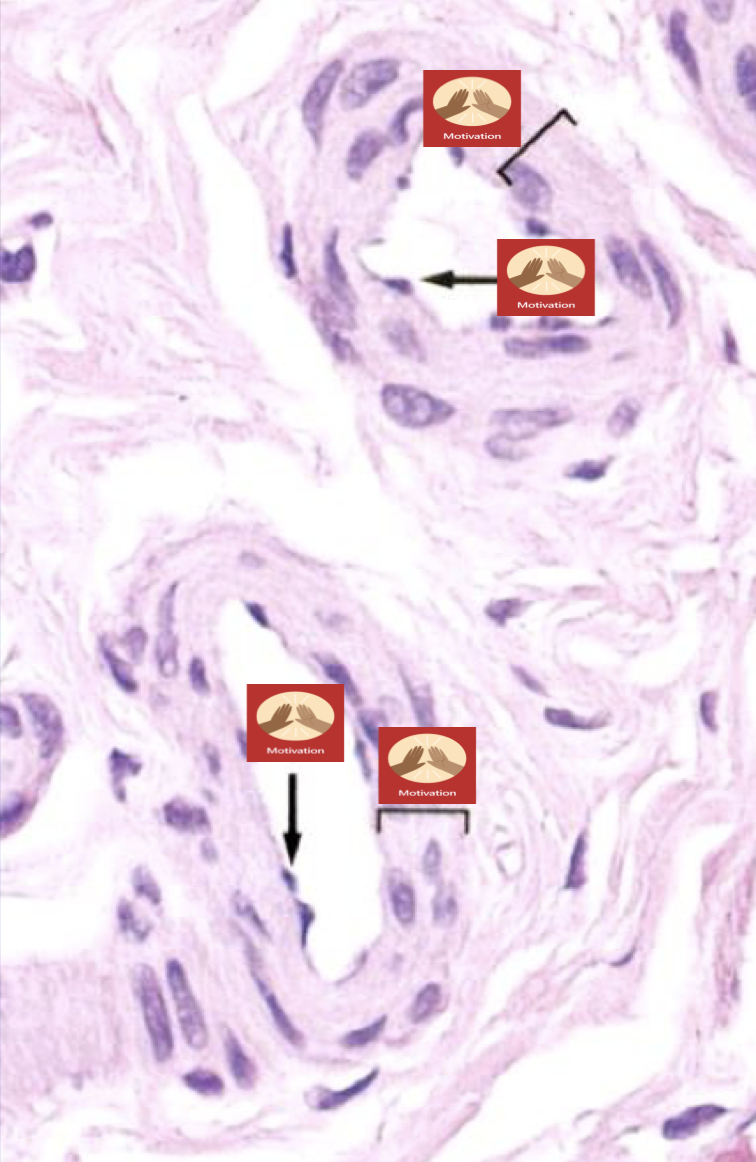

Identify (muscular artery)

24

Q

Identify (2 arterioles)

A

M = tunica media

E = endothelial cells